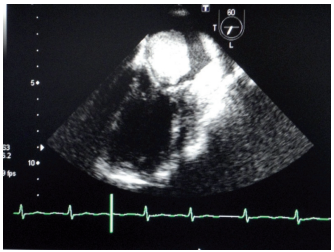

Coronariografía en el mixoma

IMÁGENES EN CARDIOLOGÍA